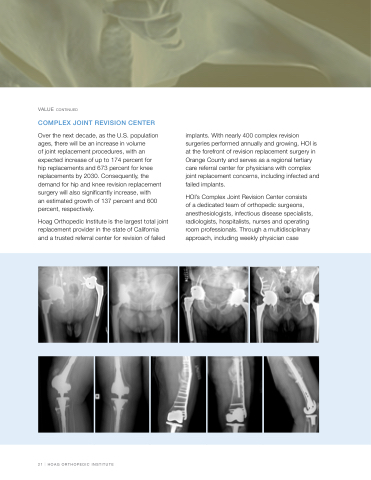

COMPLEX JOINT REVISION CENTER

Over the next decade, as the U.S. population ages, there will be an increase in volume

of joint replacement procedures, with an expected increase of up to 174 percent for hip replacements and 673 percent for knee replacements by 2030. Consequently, the demand for hip and knee revision replacement surgery will also significantly increase, with

an estimated growth of 137 percent and 600 percent, respectively.

Hoag Orthopedic Institute is the largest total joint replacement provider in the state of California and a trusted referral center for revision of failed

implants. With nearly 400 complex revision surgeries performed annually and growing, HOI is at the forefront of revision replacement surgery in Orange County and serves as a regional tertiary care referral center for physicians with complex joint replacement concerns, including infected and failed implants.

HOI’s Complex Joint Revision Center consists of a dedicated team of orthopedic surgeons, anesthesiologists, infectious disease specialists, radiologists, hospitalists, nurses and operating room professionals. Through a multidisciplinary approach, including weekly physician case